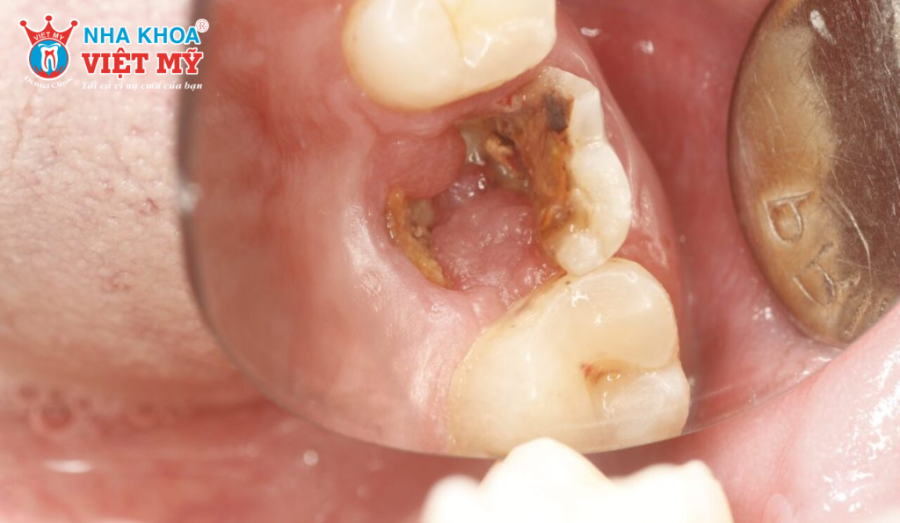

- Sâu răng tiến triển: Sâu răng không được điều trị kịp thời sẽ làm men răng và ngà răng suy yếu khiến răng dễ bị vỡ khi ăn nhai.

Nếu răng hàm bị vỡ sâu làm lộ tủy hoặc gây viêm tủy thì điều trị nội nha là bắt buộc. Bác sĩ sẽ loại bỏ phần tủy viêm, làm sạch và trám bít hệ thống ống tủy bằng vật liệu chuyên dụng (thường là Gutta-percha). Sau đó, răng thường được phục hình bằng mão sứ để tăng độ bền và tránh gãy vỡ thêm.